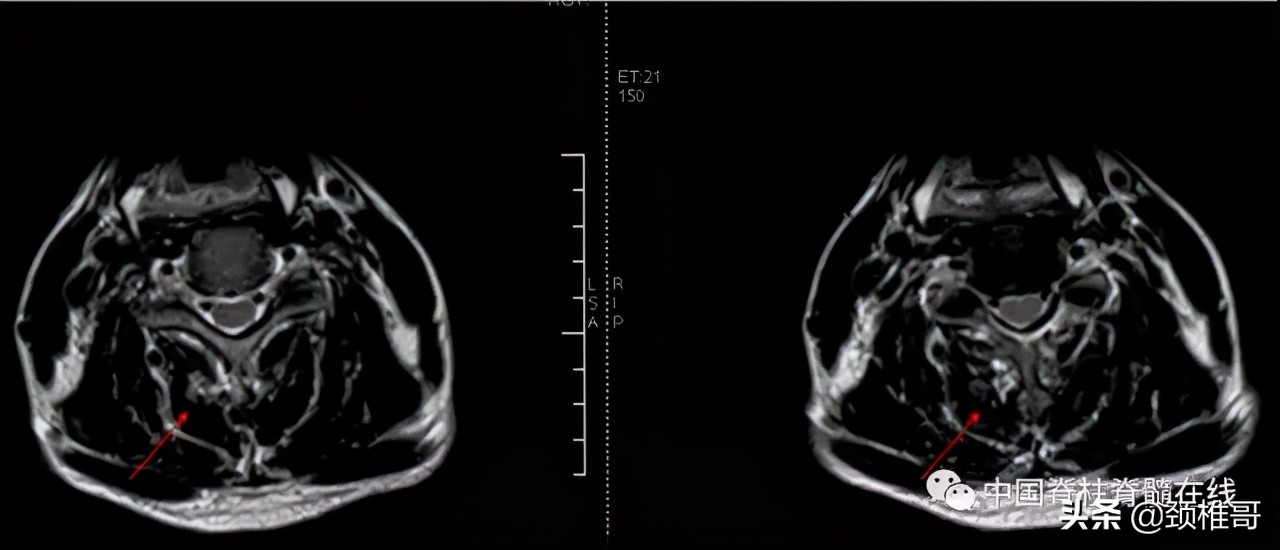

脊髓型颈椎病是一种最严重类型的颈椎病,是在肌肉、韧带、椎间盘、骨和关节都已经发生退变,颈椎动态不稳和静态不稳同时存在,代偿性的增生、钙化、韧带肥厚等综合作用下,椎管狭窄,脊髓受压所导致的一种类型颈椎病。在慢性压迫的基础上,轻度的外伤就会导致瘫痪,有的病人甚至在咳嗽、喷嚏后发生瘫痪。因此,这型颈椎病需要把握手术时机,该手术时尽早手术,否则,一旦发生瘫痪之后,四肢感觉运动、大小便功能很难恢复。在手术之后,一定进行正规的康复,否则,在手术部位的相邻节段还会继续发生退变、不稳、增生、脊髓受压等而需要一而再,再而三的手术。

脊髓型颈椎病患者会在轻轻受伤之后发生瘫痪